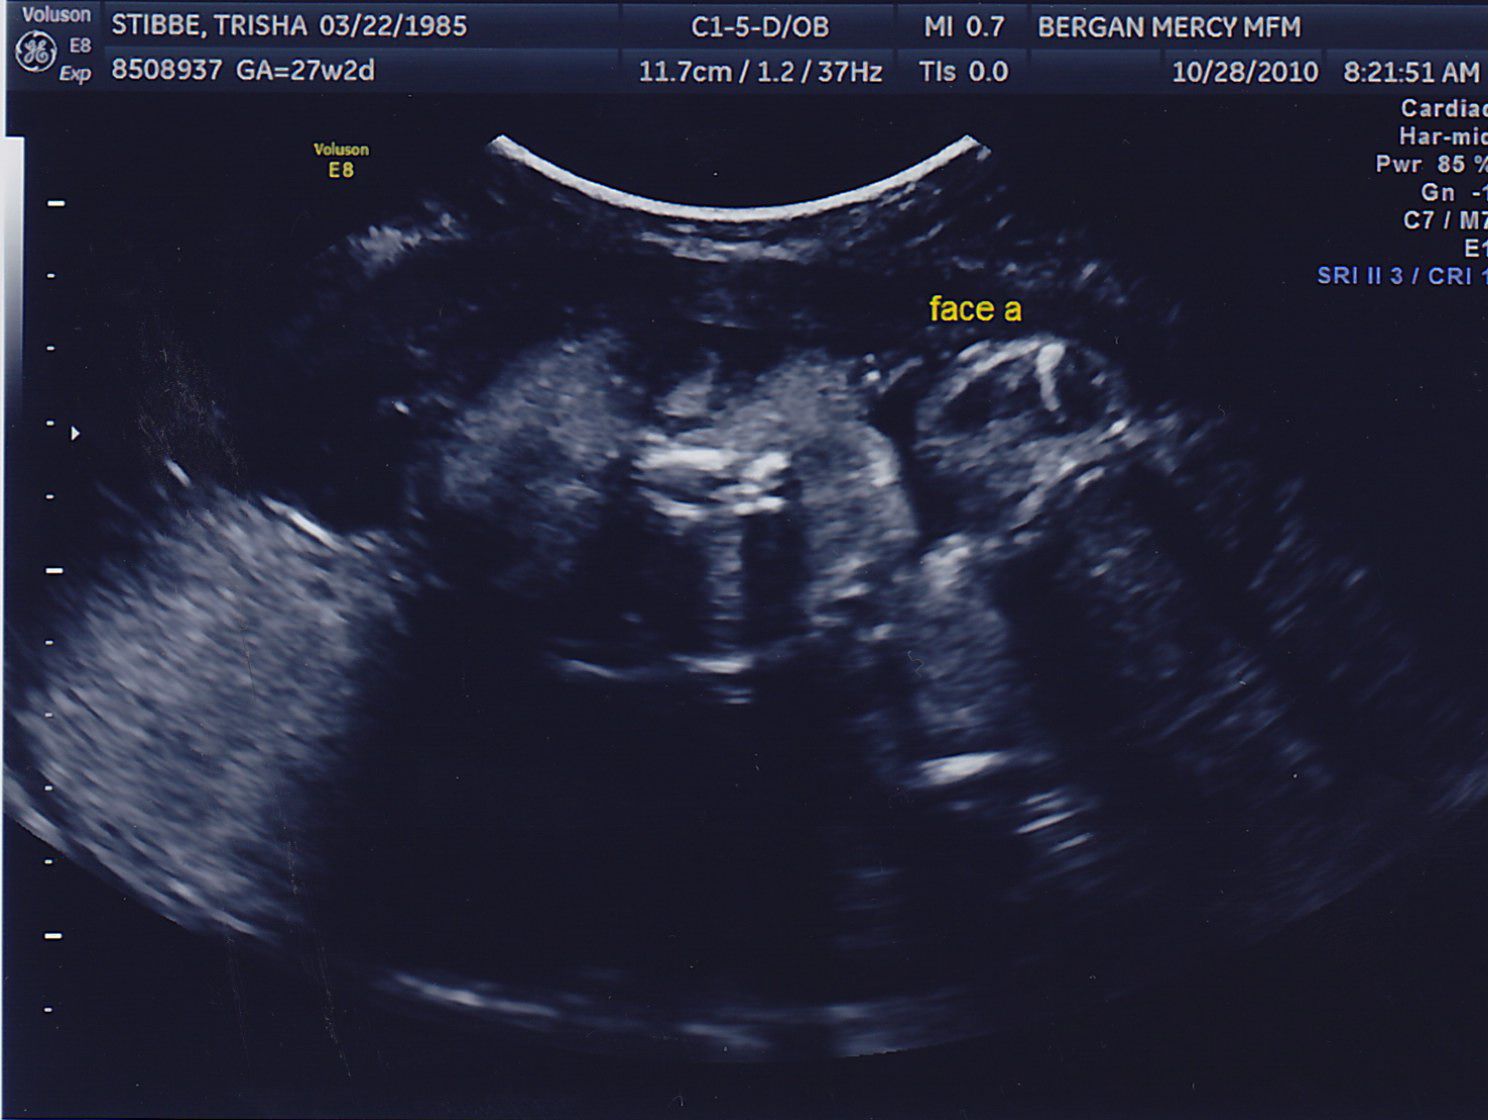

The little guys just haven’t been photogenic lately, but here’s a few pictures…